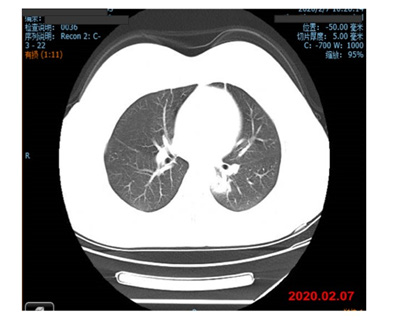

History of present illness: 4 days before admission, the patient developed fever without obvious stimulus and her body temperature reached as high as 38.5℃. She experienced sputum, tightness in the chest, shortness of breath, and no cough, anorexia, nausea, vomiting, or diarrhea. The patient went to the outpatient clinic of our hospital on 2020-02-07. The lung CT showed infectious lung lesions. The blood test showed: white blood cells: 3.62×109/L, neutrophils 1.70×109/L, lymphocytes 1.44×109/L, CRP 0.58 mg/L; the outpatient department was admitted to the hospital with possible “COVID-19 pneumonia”.

Admission physical examination: T 37.8℃, P 86 bpm, R 20 times/min, BP 120/86 mmHg, SPO2 98%. Consciousness, physical examination and cooperation. The patient has mild fatigue, no obvious yellow staining of the skin and sclera, no cyanosis of the lips, soft neck, heart rate 86 beats/min, flat and soft abdomen, no tenderness and rebound pain, under the ribs of the liver and spleen, and no percussion pain in the kidneys. There is no edema in both lower limbs, and the double Pap sign is negative (Figure1).

Figure 2: 2020.02.07 Lung CT showed infectious lung lesions and multiple ground-glass lesions in both lungs.